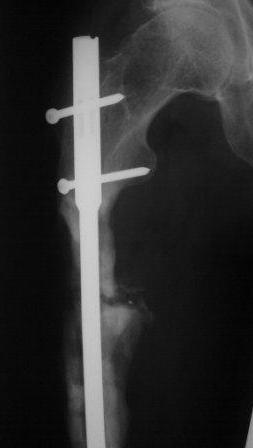

Представляю контрольные послеоперационные рентгенограммы. Во время операции была выделена зона перелома небольшим разрезом, произведена декортикация. Окончательный остеосинтез.

Все участникам обуждения большое спасибо за советы и рекомендации.

На снимках все выглядит хорошо, поздравляю. Декортикацию только делали напрасно, но уж что сделано, то сделано.

В каком состоянии был канал? Как вскрывали? Брали ли посев из зоны несращения? Зафиксировали винтами после компрессии? Или в нейтральном положении? Может, стоило динамически сразу сделать, или были какие-то соображения в пользу статического запирания?